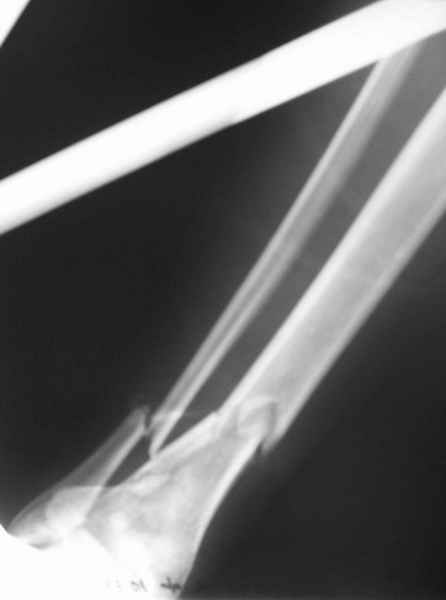

Открытый оскольчатый перелом н/3 голени.

Здравствуйте, коллеги! 16/10/06 г. В отделение поступила больная с производственной травмой - Открытый оскольчатый перелом метафиза и метадиафиза обеих костей правой голени со смещением отлоков.

Здравствуйте коллеги! В данной ситуации я полностью согласен с мнением Александра Николаевича! Практически любой внутрисуставной(тем более приведенный на снимках) перелом требует открытой репозиции.Судя по приведенным рентгенограммам, в области дистального тибио-фибулярного сочленения имеется "минус" ткань на tibia, которая может потребовать костной пластики.Метод фиксации любой,главное ранние движения в суставе. С уважением Руслан Ш.

К слову, тема этого обсуждения обозначена неточно, тут перелом дистального суставного конца типа 43-C, а не "открытый оскольчатый перелом н/3 голени", т.е. диафизарный, 42-.

Действительно, речь идет о сложном внутрисуставном, да еще и открытом переломе 43С.3.